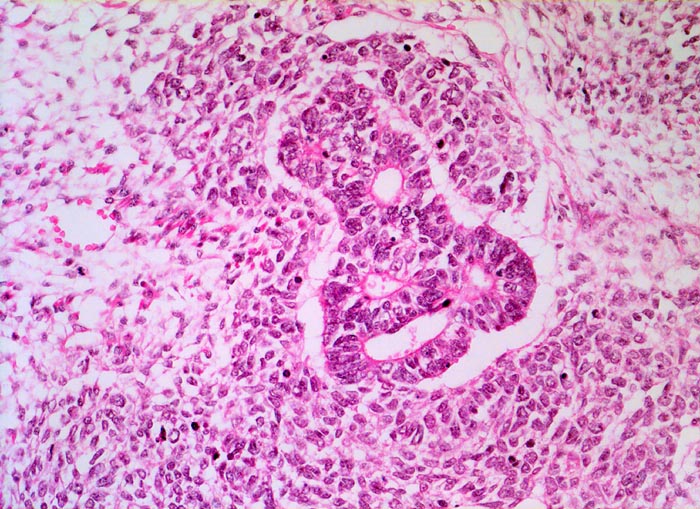

Wilms-Tumor

Komplexe kribriforme epitheliale Strukturen innerhalb des zellreichen Blastems.

Graubrauner scharf begrenzter weicher Tumor mit fokalen Nekrosen und Einblutungen.

Histologie

200